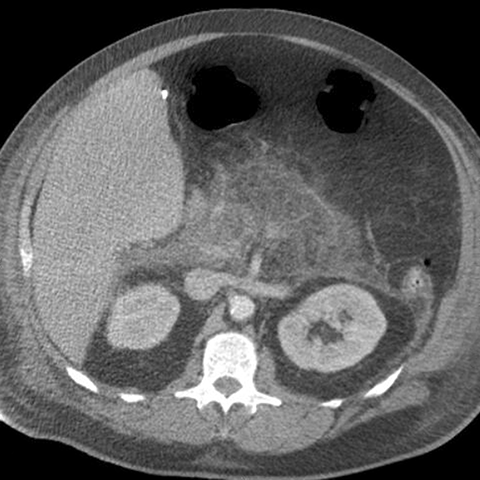

32-year-old man with severe epigastric pain after heavy partying [1 of 2]